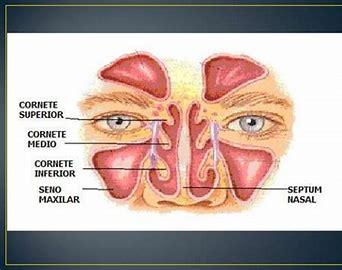

Vous croyez connaître toutes les fonctions du nez ? Cet article vous dévoilera des aspects étonnants, comme la manière dont l'air est filtré ou les effets de l'oxyde nitrique. Découvrez quelques faits surprenants sur la respiration nasale et son rôle dans le bon fonctionnement de votre corps.